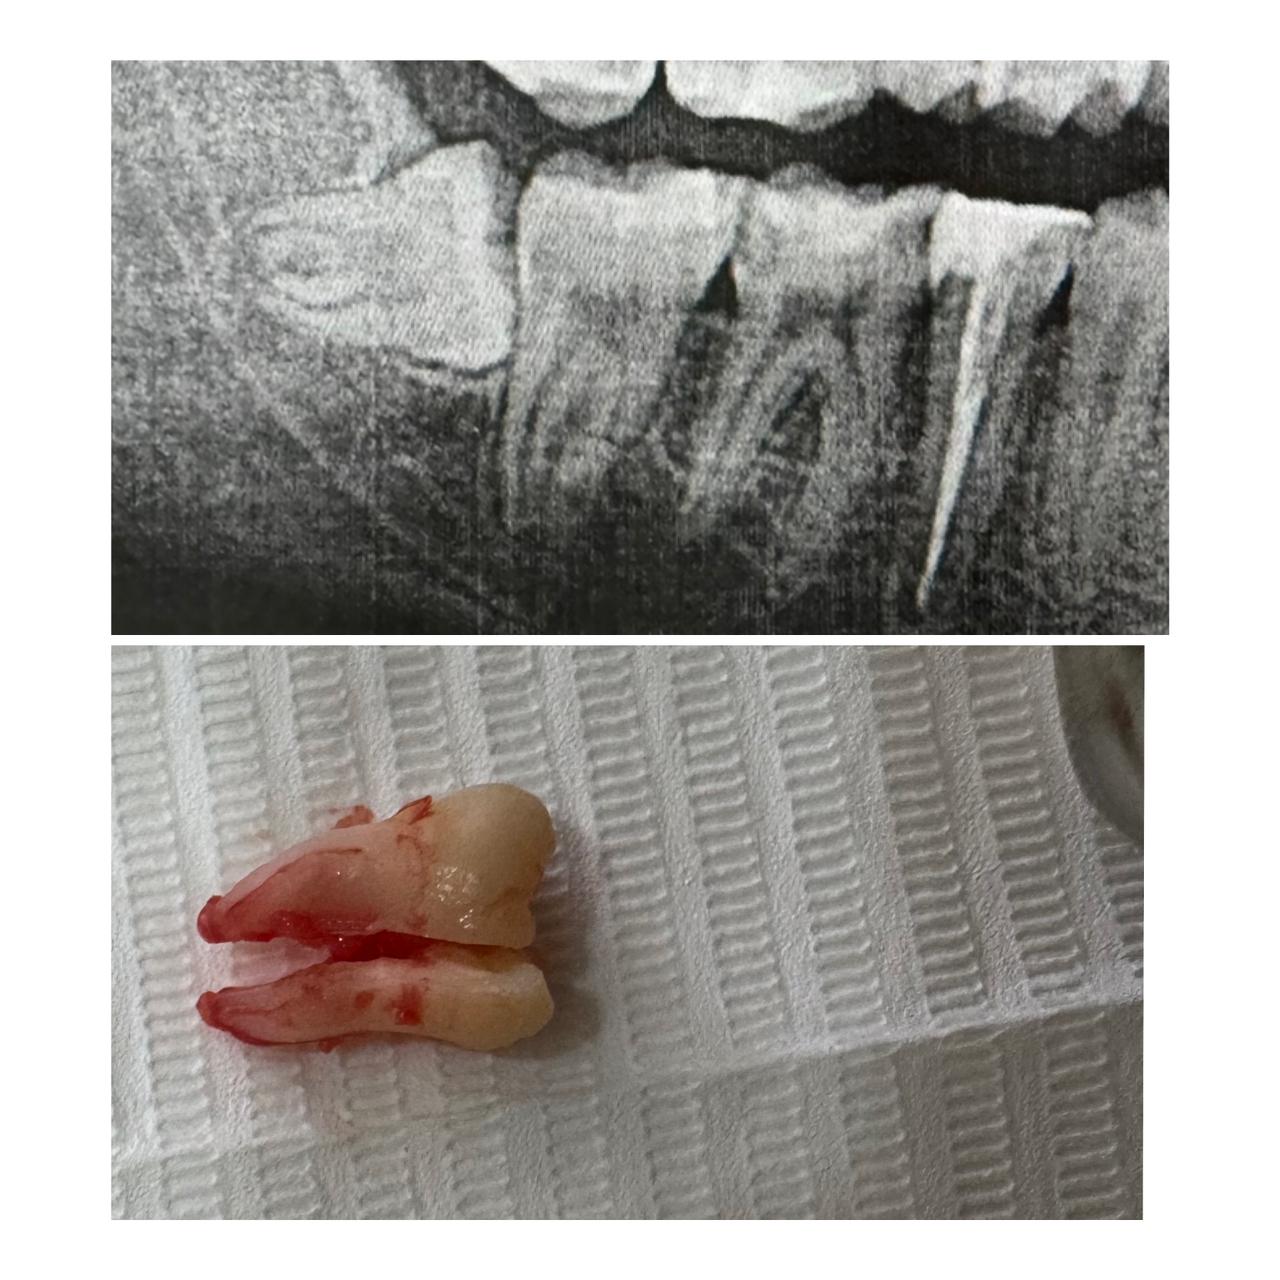

Gömülü ağıl dişlərinin çəkimi

Gömülü dişin çəkimi